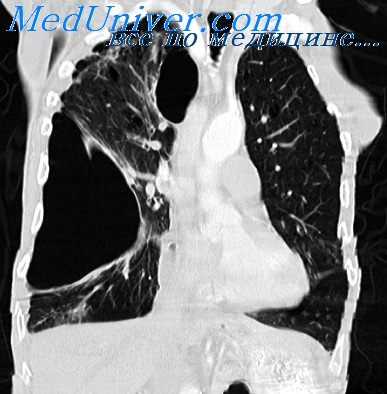

- интерлобарный (междолевой) – скопление экссудата в междолевых щелях, рентгенологически определяющееся в виде вытянутой веретенообразной тени;

Для первичного выявления осумкованного плеврита чрезвычайно важны данные полипозиционой рентгенографии грудной клетки (в прямой, боковых и косых проекциях) и рентгеноскопии легких. Рентгенологически осумкование проявляется в виде затемнения характерной локализации и формы. В сложных случаях для дифференциальной диагностики требуется наложении искусственного пневмоторакса и пневмоперитонеума, проведение КТ легких. Длительное существование осумкованного плеврита может отразиться на состоянии легочной паренхимы. Поэтому для оценки изменений прилежащих отделов легкого (бронхов, сосудов) используются рентгеноконтрастные исследования - бронхография и ангиопульмонография.

Дифференциальная диагностика различных видов осумкованного плеврита осуществляется с синдромом средней доли, ателектазом, кистой легкого, доброкачественными и злокачественными опухолями легких и средостения, субплевральными гематомами, диафрагмальной грыжей и рядом других схожих по рентгенсимеотике состояний.